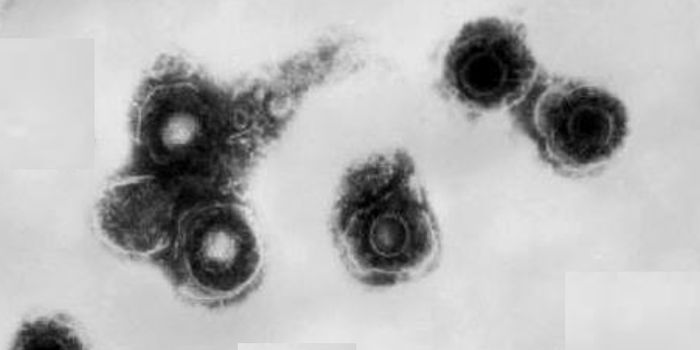

AUG 12, 2024Cell & Molecular BiologyFor many people, getting chickenpox is a rite of passage in childhood. About 95% of people carry the virus that causes i ...

JUL 15, 2024MicrobiologyMany of us experienced chickenpox as kids. The virus has a few sneaky ways to cause illness, and hang around in the body ...